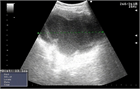

1. 下腹部痛・発熱・炎症反応上昇・膿瘍など画像所見・原因病原体の検出をもって診断する。